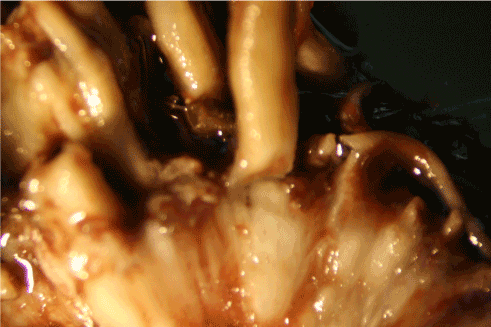

Biopsies from late proliferative stage BDD lesions were examined microscopically for comparison (Figures 5A-5D). Although the scale of filaments was much larger, the BDD filaments (roughly ten times larger) were similar in appearance compared to the specimens observed in Case 1 (Figure 5A, Figure 5B). Filaments were macroscopic, opaque and dirty white in color, ranging in size from less than 0.5 mm in diameter to about 1 mm in diameter. In cross section filaments appeared to originate beneath the stratum corneum (Figure 5C). Longer filaments were close to 1 mm in length. The BDD filaments demonstrated fluorescence under UV light (Figure 5D).

Figure 5A: Bovine digital dermatitis (BDD) sample showing coarse fibers (8x magnification).

Figure 5B: BDD sample showing floral fibers (8x magnification). Note similarity to MD floral fibers from Case 1 (Figure 2A).